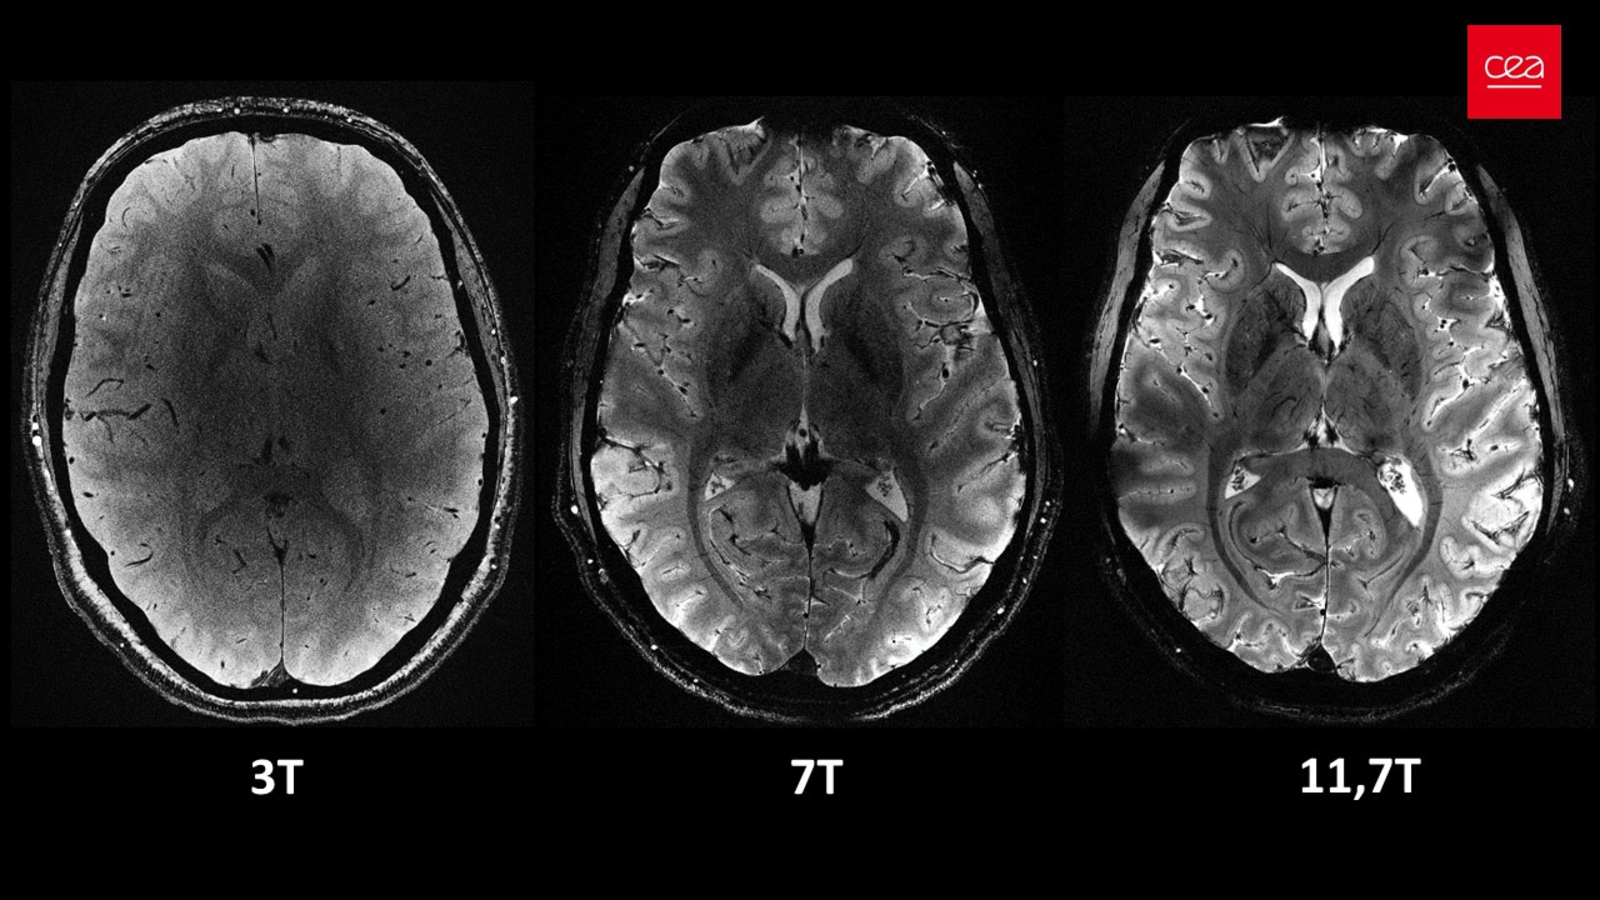

De asemenea, participanţii au fost supuşi unor evaluări cognitive şi scanări RMN.